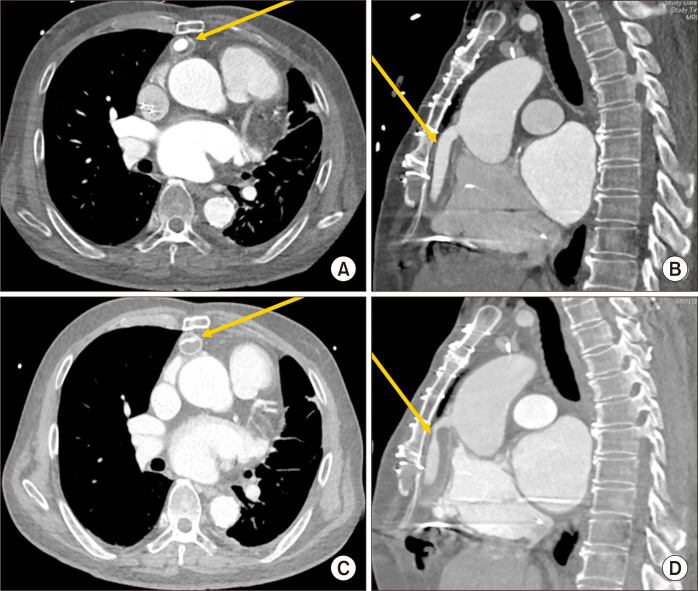

A 70-year-old man with dilated cardiomyopathy underwent left ventricular assist device (LVAD) implantation, using a HeartWare ventricular assist device, as a bridge to candidacy. After 26 months, computed tomography (CT) angiography indicated stenosis in the LVAD outflow graft; however, the patient was asymptomatic, prompting a decision to manage his condition with close monitoring. Ten months later, the patient presented with dizziness and low-flow alerts. Subsequent CT angiography revealed a critical obstruction involving the entire LVAD outflow graft. The patient underwent emergency surgery, during which an organized seroma causing the graft obstruction was found between a wrapped expanded polytetrafluoroethylene (ePTFE) graft and a Dacron outflow graft. The covering of the outflow graft was removed, along with the organized seroma. Following removal of the ePTFE wrap and decompression of the outflow graft, normal LVAD flow was reestablished. The practice of wrapping the outflow graft with synthetic material, commonly done to facilitate later redo sternotomy, may pose a risk for outflow graft obstruction.